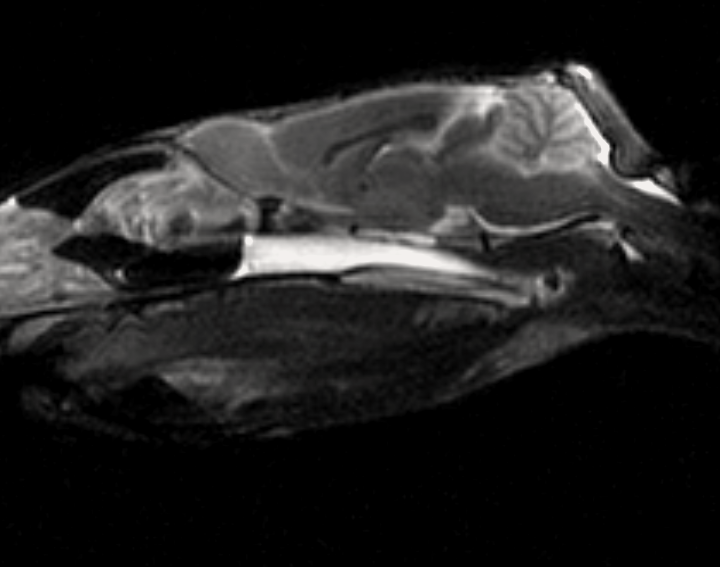

МРТ исследования проводятся на аппарате высокого качества Phillips Intera с напряженностью магнитного поля 1,5 Тесла. Позволяет максимально точно визуализировать анатомические структуры одинаково хорошо животному от 200г до 200кг

- Проведение мрт животному

- Подозрении на повреждения/ заболевания головного или спинного мозга,